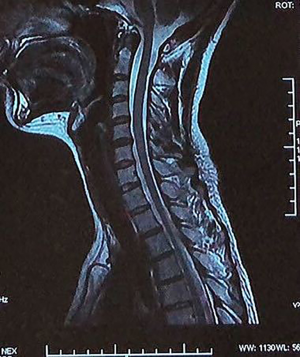

Case 2 (Figures 6 and 7 )

A 26-year-old female with a history of neck and shoulder pain for 8 years presented with a chief complaint of left side radicular pain of 7 months’ duration. Physical examination showed limited neck motion, left neck and shoulder pain, numbness with hyposensitivity in the C5 distribution, and left arm inflexibility. No specific trauma was recalled. Radiographic examination of the cervical spine showed posterior atlanto-occipital stiffness (interval ratio= ~0.81) and mild diminution in the height of the C5/6 disc space. MRI scans showed a large central herniation of the C5/6 disc, with signs of mild spinal compression. Conservative treatment was initiated for this patient.